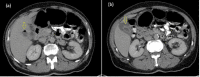

Gangrenous cholecystitis (GC) is a severe form of acute cholecystitis (AC) with ischemia and necrosis of the gallbladder (GB) wall. Patients with GC are sicker than the usual AC patients, and their surgical treatment is more complex and linked with a higher risk of morbidity and mortality. Typically, the first imaging modality used to assess patients with clinically suspected AC is ultrasound. However, if the ultrasound results were inconclusive, a CT scan might help evaluate these individuals. Our study presents a 62-year-old male who presented with mild right upper quadrant discomfort. However, an abdominal computed tomography CT scan showed a pericholecystic fluid collection with a sign of GB perforation that was managed with subtotal cholecystectomy. Five days after the operation, the patient was discharged to home in excellent condition.